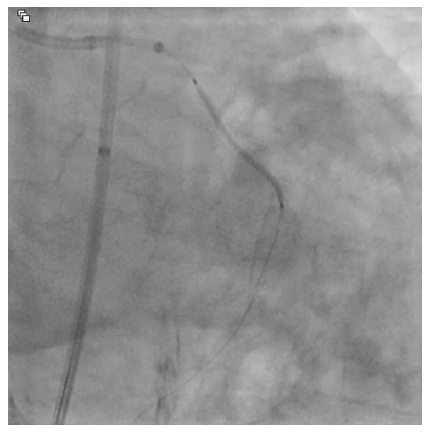

An 81-year-old male with hypertension, diabetes, and hyperlipidemia was referred for evaluation of an abnormal stress test. He originally complained of shortness of breath with exertion. A pharmacologic stress test was performed at an outside facility and showed inferior wall ischemia with a normal ejection fraction. He underwent coronary angiography via a right radial approach that revealed a heavily calcified, eccentric lesion in the large, codominant circumflex artery with TIMI-3 flow (Figure 1). Due to a small ulnar artery, the decision was made to access the right femoral artery in preparation for complex intervention. Utilizing a 6 French Judkins Left 4 guide catheter, the left system was engaged. The lesion was wired with a Runthrough® Izanai™ wire (Terumo Interventional Systems) and pretreated with balloon angioplasty using a 2.0 mm x 15 mm Takeru™ RX balloon (Terumo Interventional Systems) (Figure 2). A 2.5 mm x 15 mm Takeru™ RX noncompliant (NC) balloon was then advanced to perform further pre-dilation balloon angioplasty (Figure 3).